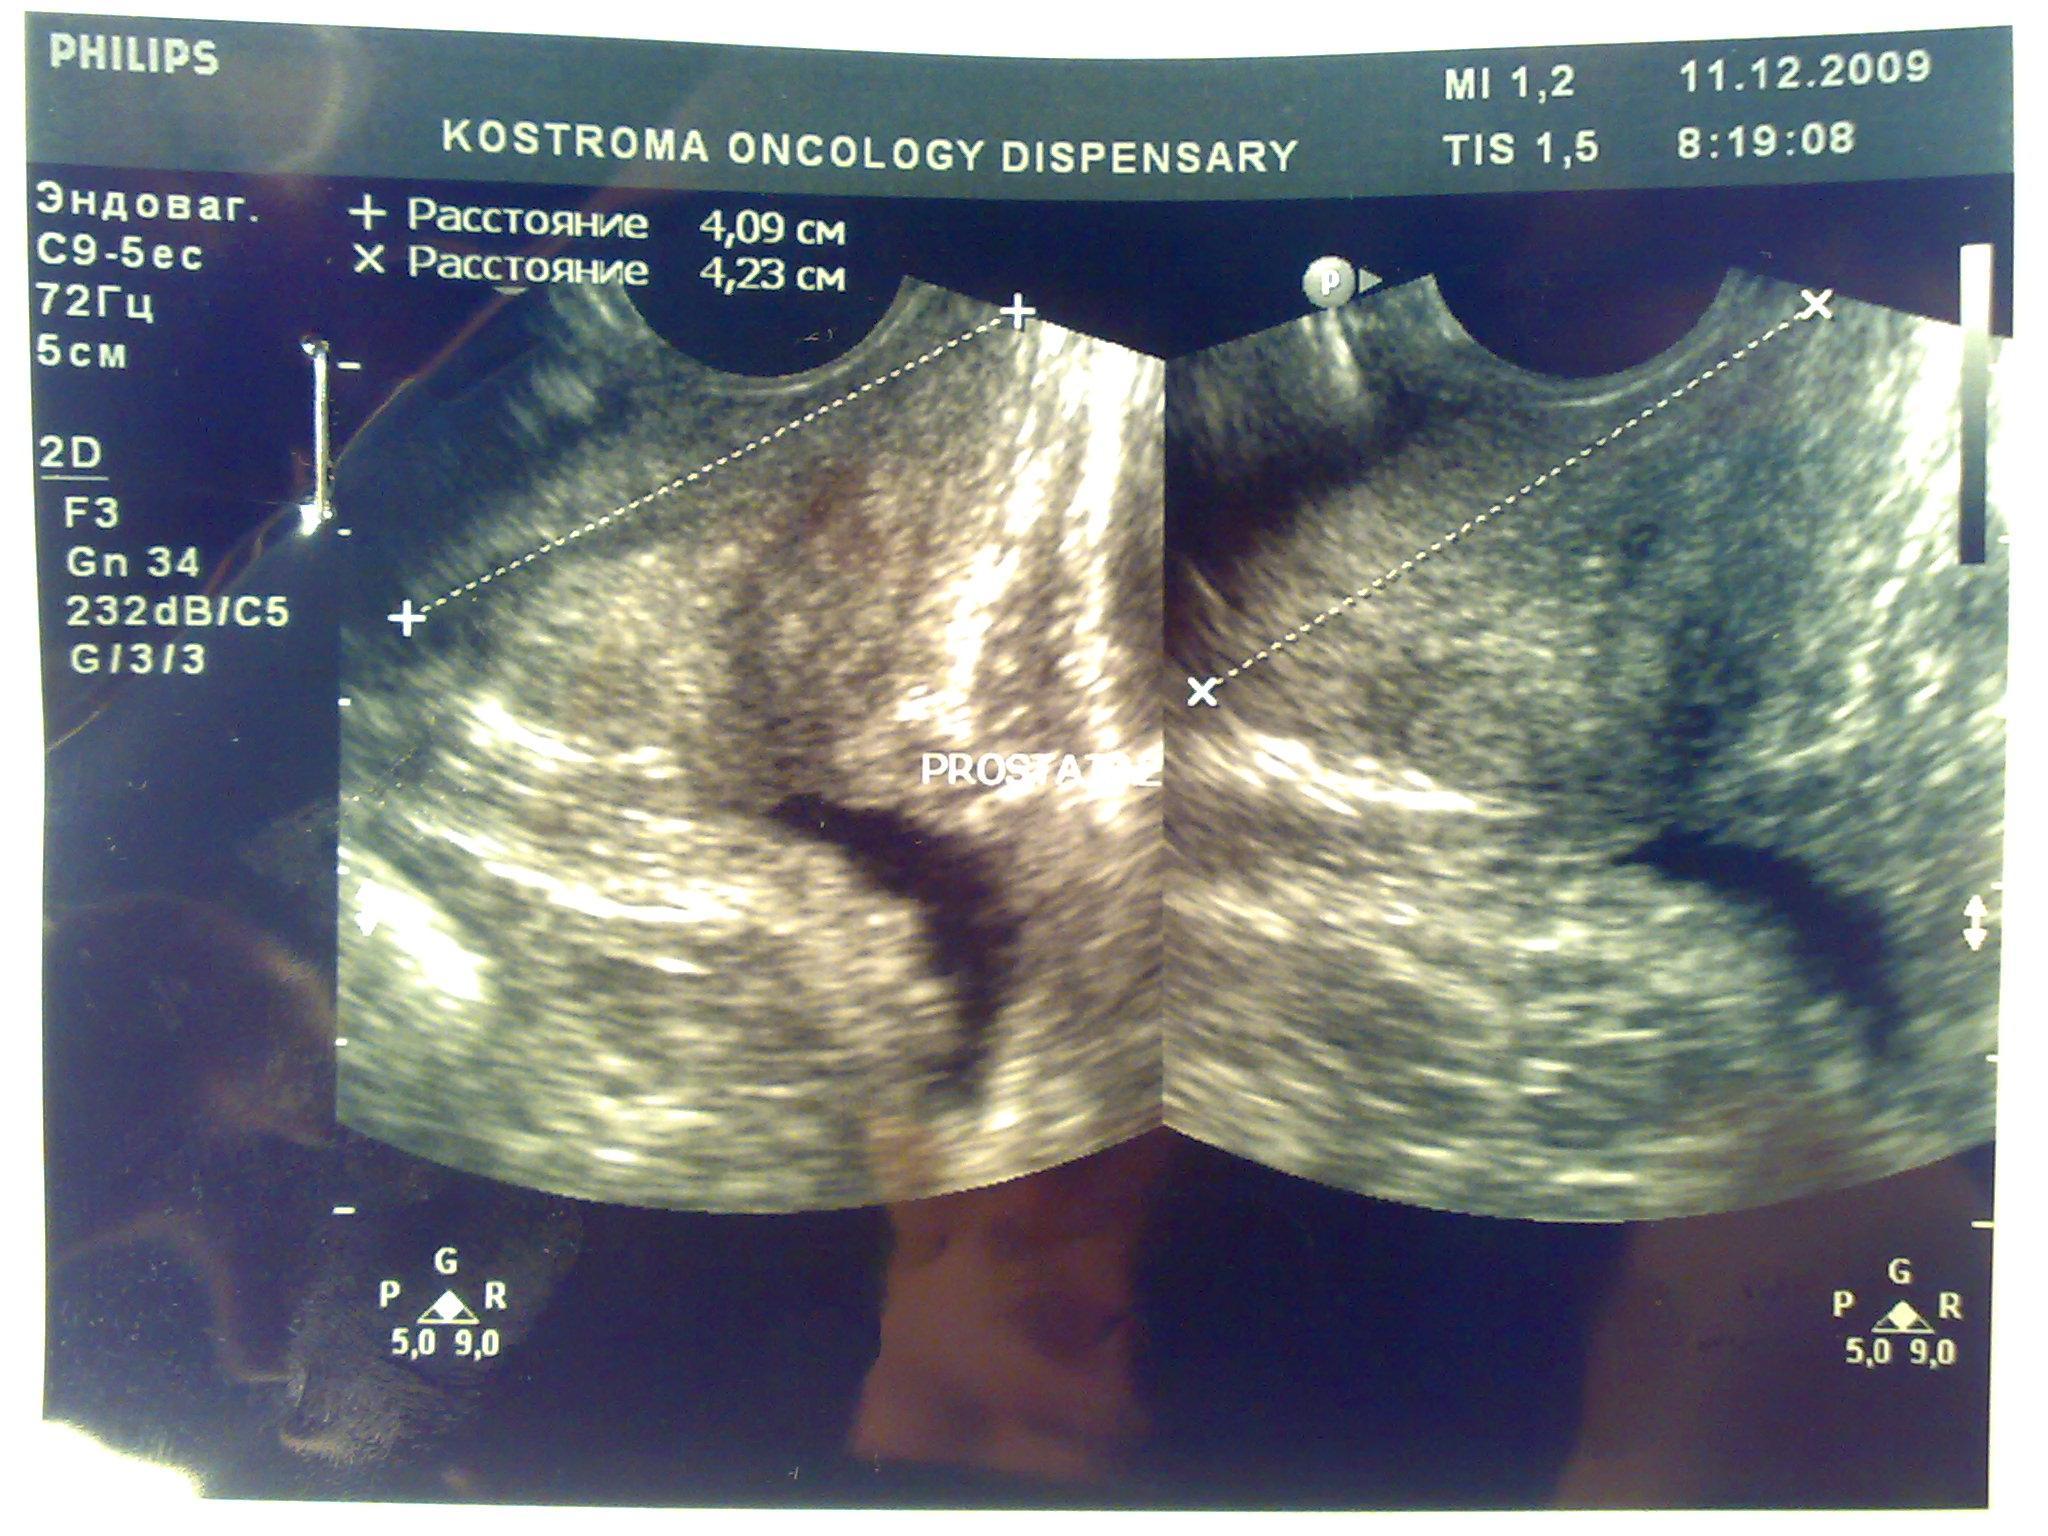

Посмотрите пожалуйста снимки узи, какие выводы можно сделать кроме увелечинных размеров? Может ли это влиять на эректильную функцию или изменение гормонального статуса? Болевых ощущений нет, есть небольшой дискомфорт, мочеиспускание в норме, но струя послабже чем была.Очень переживаю, ночами не сплю из-за нервов, без седативных уже и не уснуть.Заранее благодарен.

Ваши симтомы не связаны с предстательной железой. Вам нужен хороший психолог или психоаналитик. Уролог не нужен.